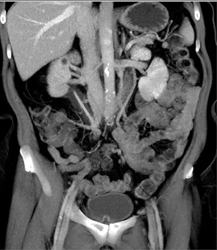

Retroperitoneal Fibrosis